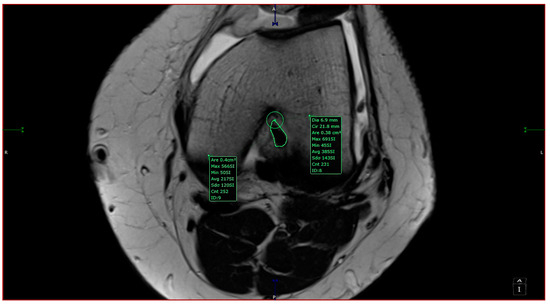

- aICN area: area of the circle defined by three cortical walls of the antero-superior notch (in the custom axial plane/CAP; Figure 3).

- ACL area: area of the closed polygon defined by pointed dots around the cross-section of the anterior cruciate ligament (in the CAP; Figure 4).

- aICN area and ACL area (both appear in Figure 6).